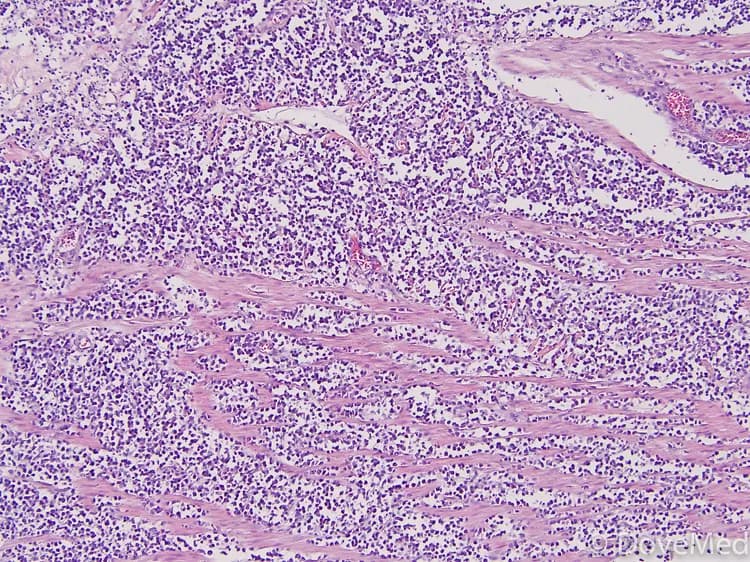

• A biopsy of the tumor is performed and sent to a laboratory for a pathological examination. A pathologist examines the biopsy under a microscope. After putting together clinical findings, special studies on tissues (if needed) and with microscope findings, the pathologist arrives at a definitive diagnosis. Examination of the biopsy under a microscope by a pathologist is considered to be gold standard in arriving at a conclusive diagnosis

• Biopsy specimens are studied initially using Hematoxylin and Eosin staining. The pathologist then decides on additional studies depending on the clinical situation

• Sometimes, the pathologist may perform special studies, which may include immunohistochemical stains, molecular testing, flow cytometric analysis and very rarely, electron microscopic studies, to assist in the diagnosis

• A tissue biopsy study of the endemic and sporadic forms of Burkitt lymphoma, generally reveals the same set of results